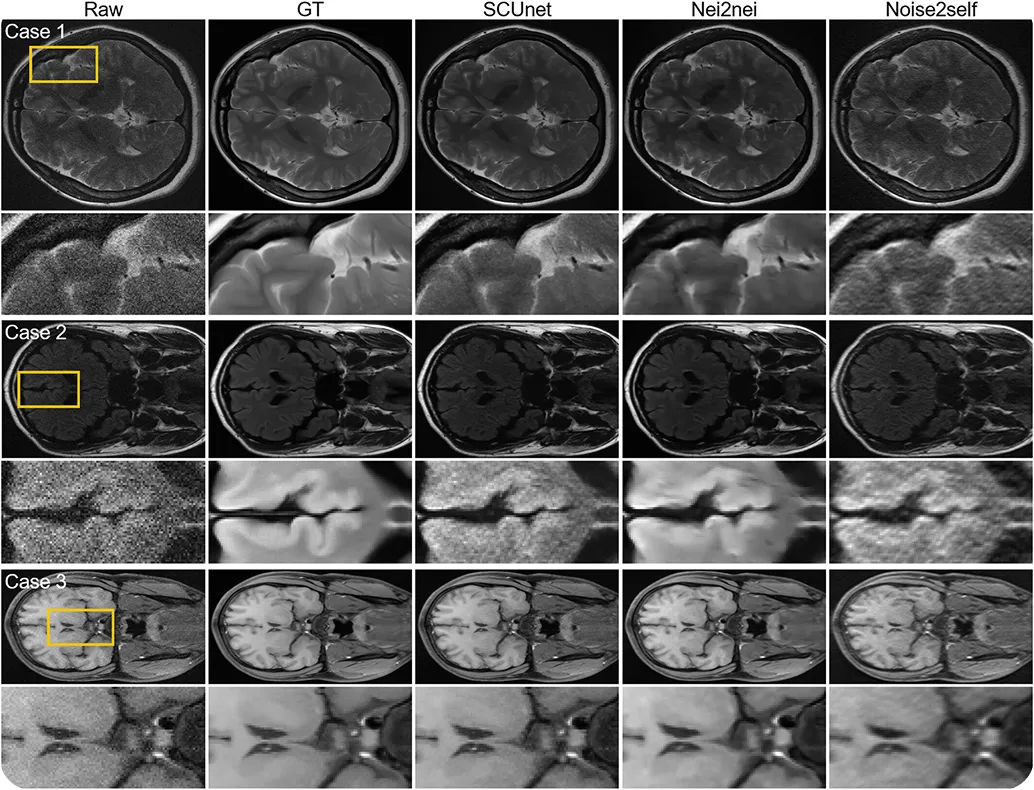

Шумы на снимках могут возникать из-за движения пациента, низкого уровня сигнала или ограничений на использование излучения. Чтобы сделать медицинские снимки более четкими, исследователи изучили методы самоконтролируемой денуации, такие как Noise2Self и другие подобные подходы.

Эти модели обучаются непосредственно на зашумленных МРТ-изображениях мозга, самостоятельно изучая шумовые паттерны и очищая их, не нуждаясь в идеально четких примерах. На обработанных изображениях более четкие текстуры и лучший контраст, что облегчает выявление мелких структур. Такие денуазеры на базе ИИ упрощают рабочий процесс в диагностической визуализации и повышают эффективность анализа в реальном времени.

Рис. 4. Использование различных методов самоконтролируемой денуации на снимках МРТ головного мозга.(Источник)